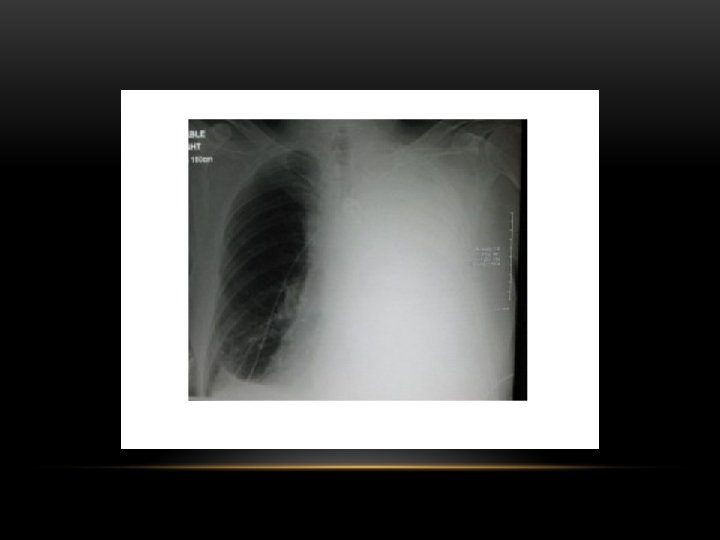

Pneumothorax • No vascular markings on right • No shift of mediastinum to left • Atelectasis right lung • Increased haziness on left: Diversion of entire cardiac output • Small fluid level near costophrenic angle: Hydro pneumothorax

Tension Pneumothorax • No vascular markings on right • Shift of mediastinum to left • Atelectasis right lung • Increased haziness on left: Diversion of entire cardiac output

Spontaneous Pneumothorax • Air in pleural space • Lung margin • "Normal lungs": Note the radiolucency of atelectatic lung is the same as the opposite lung